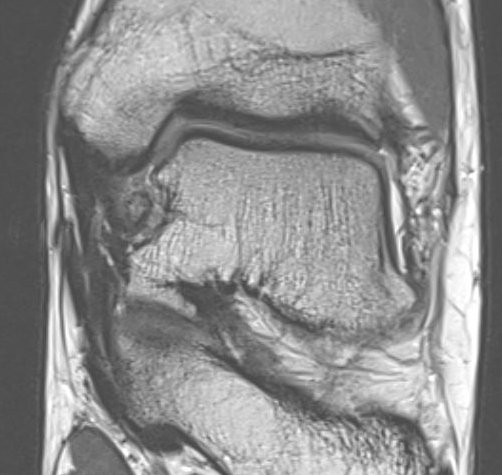

MRI

Old bony avulsion of deltoid ligament